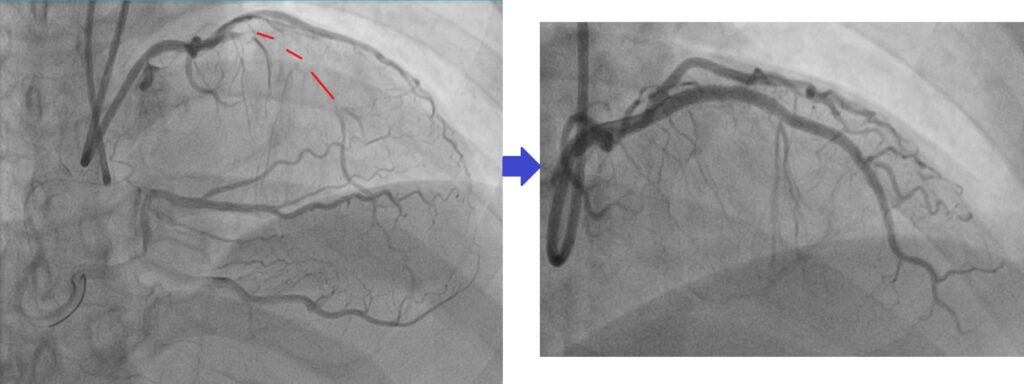

A patient of mine with CTO LAD as shown with red dotted line, after opening the CTO, can see flow to the coronary vessel.